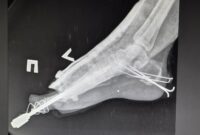

In the city of Kyiv, in July we began to provide physiotherapy services in a hospital managed by the Ministry of Interior. There are approximately 300 beds entirely dedicated to war-wounded people. The need for post-operative care is enormous, as rehabilitation and physiotherapy was not particularly developed in the local healthcare system prior to the conflict and the high number of trauma patients are at risk of developing long-term mobility issues without proper care. MSF physiotherapists work side by side with local health staff providing bedside training and creating local capacity for physiotherapy.